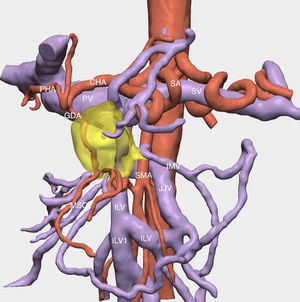

The resection of locally advanced adenocarcinoma of the pancreatic head with occlusion of the superior mesenteric vein and involvement of the splenomesenteric portal confluence (EMP) sometimes requires prolonged venous clamping with risk of intestinal ischemia. The use of intraoperative venous shunts has been published by reference groups to allow successful resection. In our centre we performed a total pancreatoduodenectomy for locally advanced pancreatic head adenocarcinoma with superior mesenteric vein occlusion (SMV) and splenomesenteric portal confluence. The use of a temporary ileo-caval shunt via a venous graft allowed resection of the tumour without repercussion on the bowel. The surgery ended with closure of the shunt, anastomosis of the graft to the portal vein and digestive reconstruction. The patient presented good tolerance to surgery and was discharged on the 7th postoperative day. The pathology report described pancreatic adenocarcinoma ypT1N0(R0) regression grade GRT2/IIa, with 0/30 affected adenopathies.

La resección de adenocarcinoma de cabeza de páncreas localmente avanzado con oclusión de la vena mesentérica superior y afectación del confluente esplenomesentéricoportal (EMP) obliga en ocasiones a un clampaje venoso prolongado con riesgo de isquemia intestinal. La utilización de shunts venosos intraoperatorios ha sido publicado por grupos de referencia para permitir la resección con éxito. En nuestro centro realizamos una duodenopancreatectomía total por adenocarcinoma de cabeza de páncreas localmente avanzado con oclusión de vena mesentérica superior (VMS) y confluente esplenomesentéricoportal. El uso de un shunt ileo-caval transitorio mediante un injerto venoso permitió la resección del tumor sin repercusión en el intestino. La cirugía finalizó con el cierre del shunt, anastomosis del injerto a la vena porta y reconstrucción digestiva. El paciente presentó buena tolerancia a la cirugía, siendo dado de alta el 7 ° día postoperatorio. El estudio anatomopatológico describió adenocarcinoma pancreático ypT1N0(R0) grado regresión GRT2/IIa, con 0/30 adenopatías afectas.